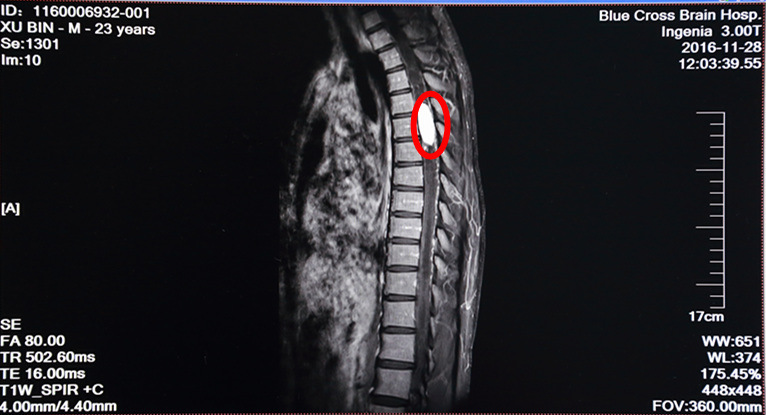

術前MRI增強掃描:紅圈內(nèi)白色物體為腫瘤,腫瘤兩極廣泛性脊髓空洞

病人徐某,23歲,雙下肢失去知覺,行走不能1月半。在其他醫(yī)院檢查診斷為胸4--6段脊髓內(nèi)血管母細胞瘤,屬于最困難且風險很大的脊髓病變手術,該區(qū)域是椎管最狹窄,脊髓血供相對較豐富的部位。另外,病人第四腦室及右側(cè)海馬區(qū)顳角位置也發(fā)現(xiàn)有腫瘤,四腦室明顯擴大、腫瘤明顯壓迫腦干。病家曾找我國最知名的一位脊髓外科專家看過,認為風險巨大,遂到我院尋求治療,做增強MRI及DSA見腫瘤血供極其豐富,椎管內(nèi)幾乎僅見腫瘤而看不見正常的脊髓組織結(jié)構(gòu)。